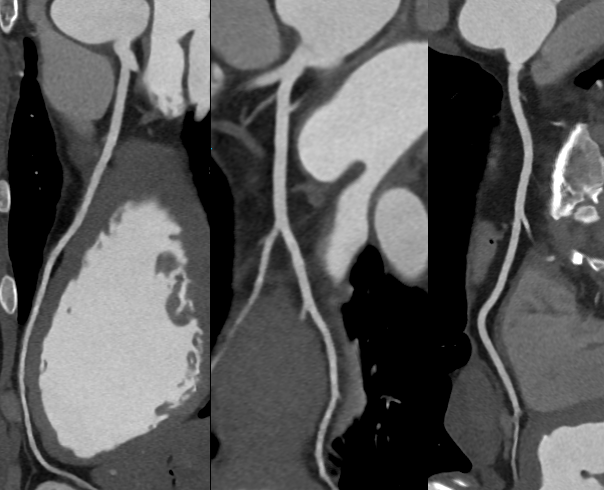

「全域」心脏多模态高清成像

全新双宽体CT系统uCT SiriuX凭借全脏器覆盖能力,实现 “全域” 心脏多维成像评估,即注射一次对比剂可同时获取冠脉CTA、心肌灌注、心脏能谱成像和心肌延迟强化等多维图像信息,初步验证结果与DSA、MR心肌灌注、MR延迟强化等金标准影像手段有较高一致性。这对于需要同时进行解剖与功能性评估的患者来说,方便省事了许多。

冠脉CTA  VS DSA